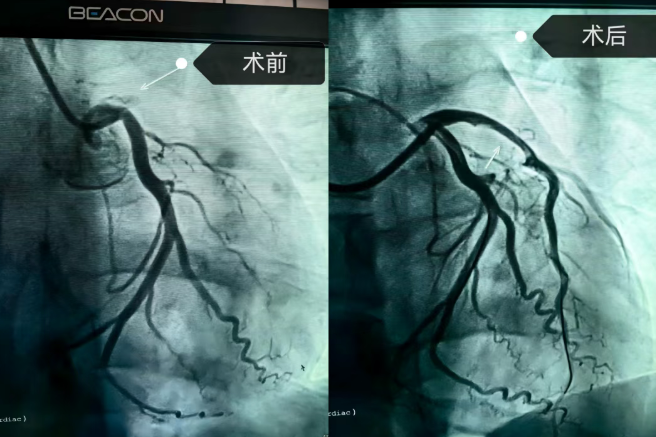

医院立即启动胸痛绿色通道,迅速激活导管室。在转运过程中,患者突发心脏骤停,医疗团队立即进行心肺复苏并成功电复律。随后冠脉造影显示,前降支近段完全闭塞。考虑患者年轻、对生活质量要求高,心血管病科团队决定采取“介入无植入”方案,通过血栓抽吸、冠脉内溶栓及球囊扩张成形术,成功实现血管再通。

术后一周复查显示,前降支仅存轻度狭窄,患者接受强化药物治疗、危险因素管控及系统心脏康复。该治疗方案不仅避免了体内植入物,减轻患者长期心理负担,也最大程度保留了血管原有功能。